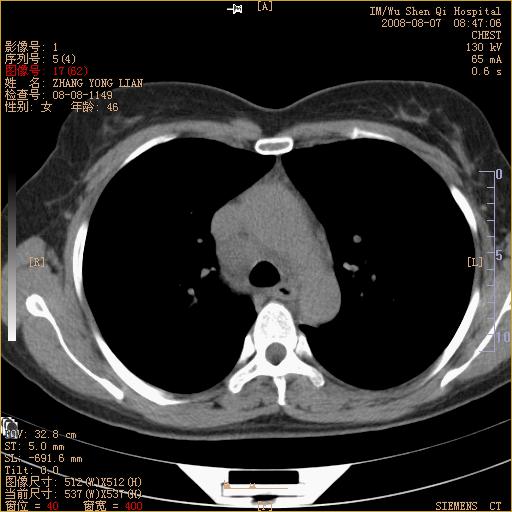

标题: CT15050:女,46岁,咳嗽胸痛一月余 [打印本页]

标题: CT15050:女,46岁,咳嗽胸痛一月余

纵隔窗没发全,左下肺近胸膜处结节。有长毛刺,纵隔淋巴结增大,不排除恶性病变。

考虑肺癌

考虑左肺下叶后基底段周围型肺癌伴纵隔淋巴结转移可能性大。

左下肺ca并纵隔及左肺门区淋巴结转移。

脾脏低密度结节转移不排除。

1)考虑左肺下叶后基底段周围型肺癌伴纵隔淋巴结转移。2)脾内低密度灶,性质待定;不排除转移瘤可能。

考虑左肺下叶后基底段周围型肺癌伴纵隔及肺门淋巴转移。